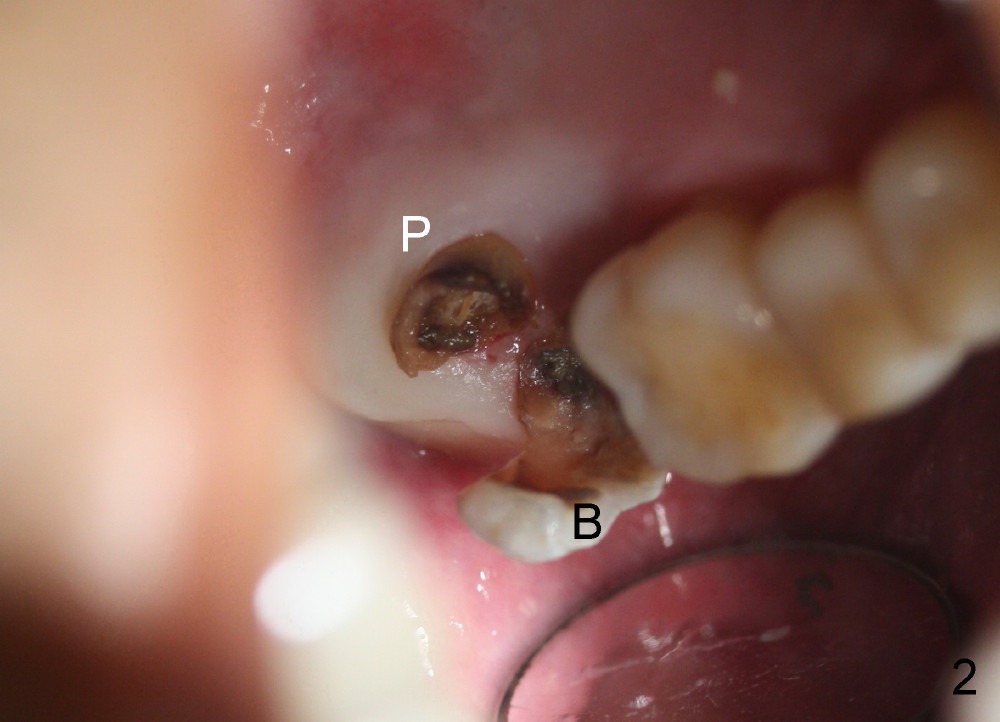

Immediately preop PA and photo confirm that the upper right 2nd molar is nonsalvageable (Fig.1,2). After extraction, it appears that there are 3 potential sites for immediate implant.

The buccal socket (Fig.3 B) is large and shallow (difficult to achieve primary stability of implant); the palatal wall of the buccal socket is apparently thin (greyish *). The most critical is that the buccal plate of the buccal socket is low (Fig.10a).

By contrast the palatal socket is deep and relatively small (Fig.4 P), easy to insert taps without drills. When a 7x11 mm tap is placed (Fig.5 T), the coronal end is more or less near the lingual cusps (functional cusps). Although the 7x14 mm tap (Fig.6 T) and a 7x11 mm implant (Fig.7 I) look poking into the maxillary sinus, they are in fact within the palatal socket (Fig.10c). Allograft and Osteogen are placed in the buccal socket (Fig.7 *), followed by collagen dressing (Fig.8 *). A 5x5 mm abutment is placed (Fig.8 A). An immediate provisional (Fig.9 P) is cemented to keep the graft and collagen dressing in place.